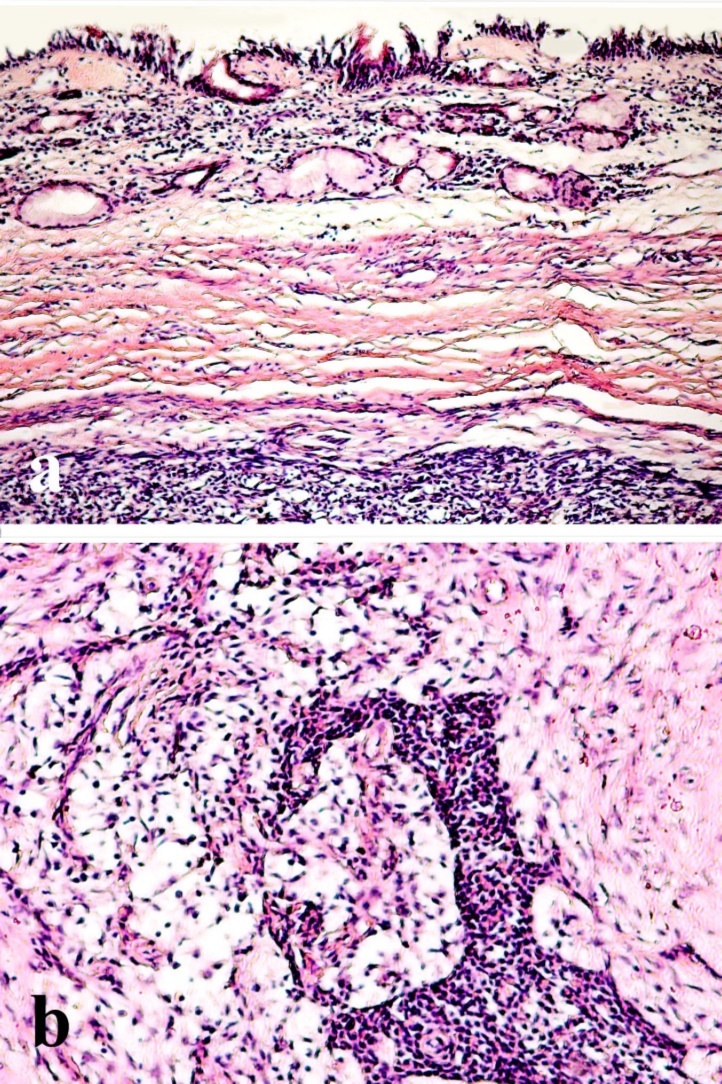

The final histopathologic result for the tumor, in all cases, was pleomorphic adenoma, and the resection margin was tumor free. The tumor was composed of abundant polygonal epithelial and spindle-shaped myoepithelial elements in a myxofibrous stroma (Figure 2).

Figure 2.a-Histopathologic section showing a benign non-encapsulated tumor under respiratory epithelial lining b-The tumor is composed of polygonal epithelial and spindle-shaped myoepithelial elements in a myxofibrous stroma (H&E, x200

Diagnosis of intranasal pleomorphic adenomas mainly relies on pathologic examination. Pleomorphic adenomas are characterized by epithelial tissue mixed with mucoid and myxoid elements. However in nasal pleomorphic adenomas, myoepithelial cellularity is increased compared with major salivary gland tumors. This may cause difficulty in its histopathologic diagnosis as pointed to by Compagno and Wong5as well as Shih-Hung.13Haberman and Stanely14reported a case of a nasal pleomorphic adenoma misdiagnosed as adenoid cystic carcinoma on the basis of tissue biopsy. Many authors have speculated the pathogenesis of these tumors. It was suggested that nasal pleomorphic adenomas originate from the remnants of vomeronasal (Jacobson’s) organ. However, these adenomas may arise from the lateral nasal wall, where no such organ exists. Evan and Cruickshank15contradicted the previous theory and suggested that these tumors are entirely epithelial tumors that arise in fully developed gland tissue. Malignant transformations and distant metastasis of these tumors are uncommon.16 However, Freeman et al17reported a case of carcinoma ex-pleomorphic adenoma, and Cho et al18reported another 2 cases. These reports highlight the importance of careful histopathologic examination of the specimens.